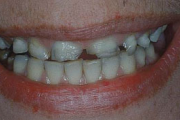

Puudub ülemine tsentraalne intsisiiv, kuid külgmised lõikehambad on juba lõikunud.

Turritavad ülemised lõikehambad.